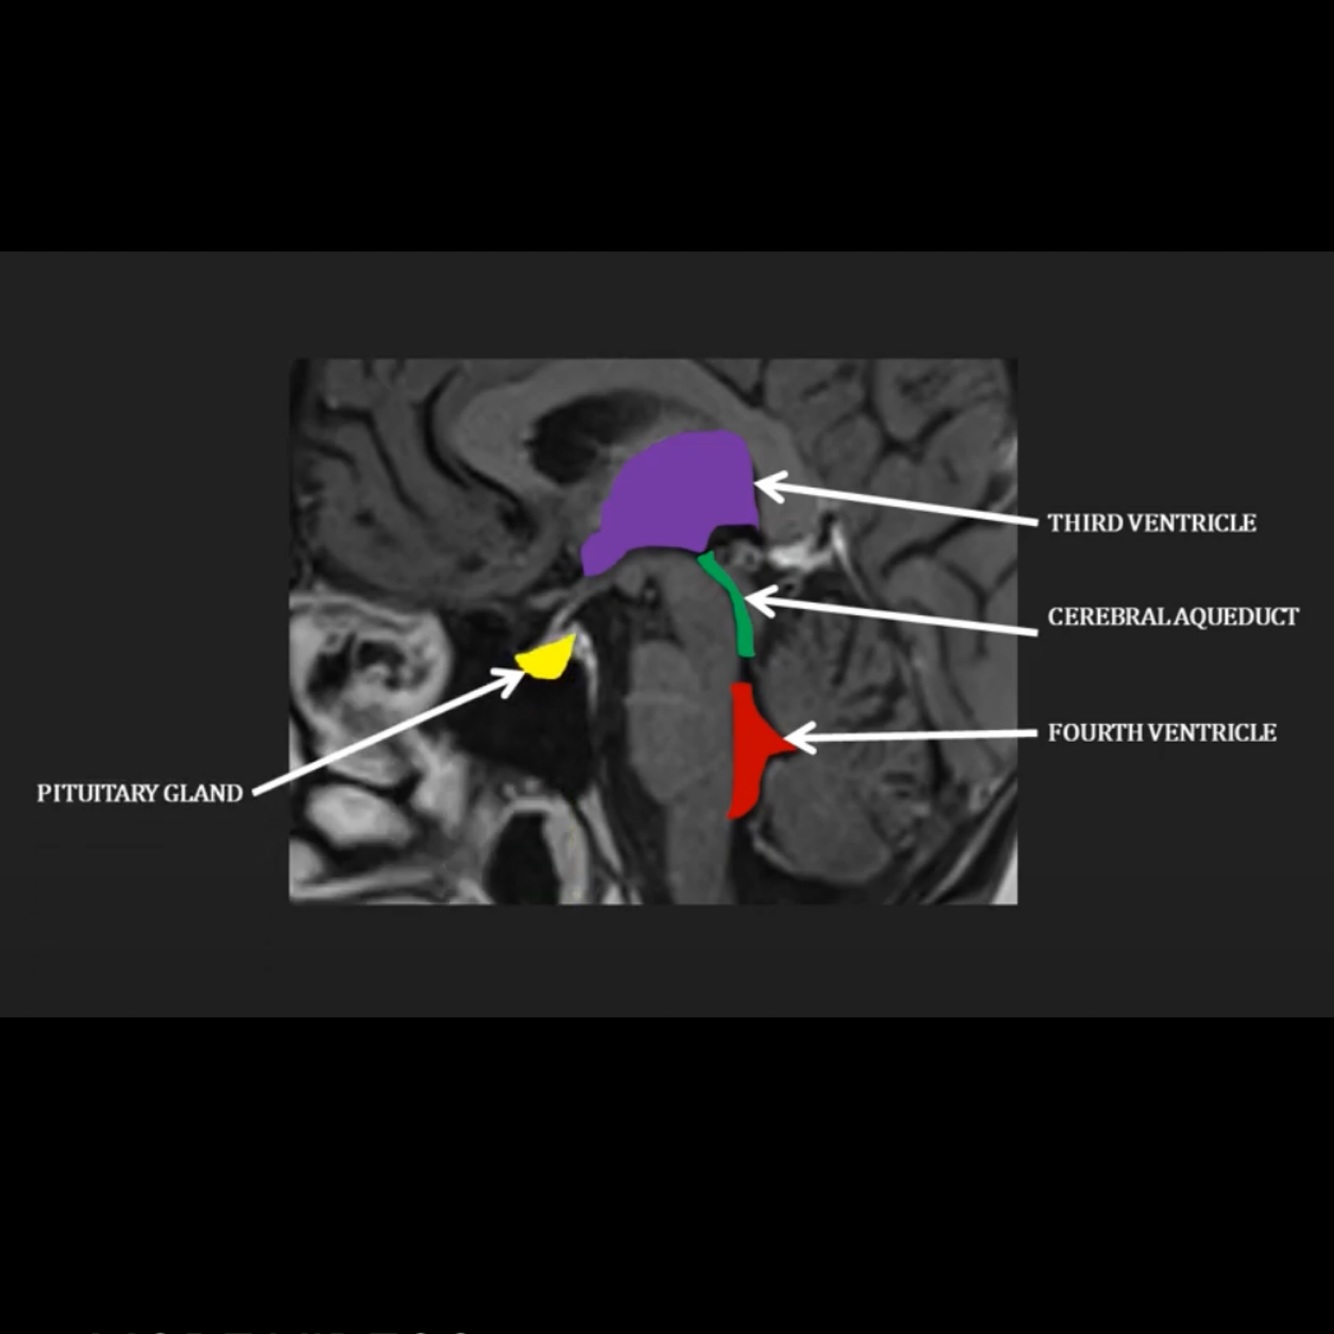

Where does the CSF flow through the brain as visible on this diagram?

Through the third ventricle into the cerebral aqueduct, into the fourth ventricle

Where does the pituitary gland sit in relation to the ventricles?

Where is the pituitary stalk?

Anteriorly in the pituitary fossa

Pituitary stalk superior to pituitary gland

Where does the optic chiasm sit in relation to the pituitary gland?

Immediately superior to pituitary stalk